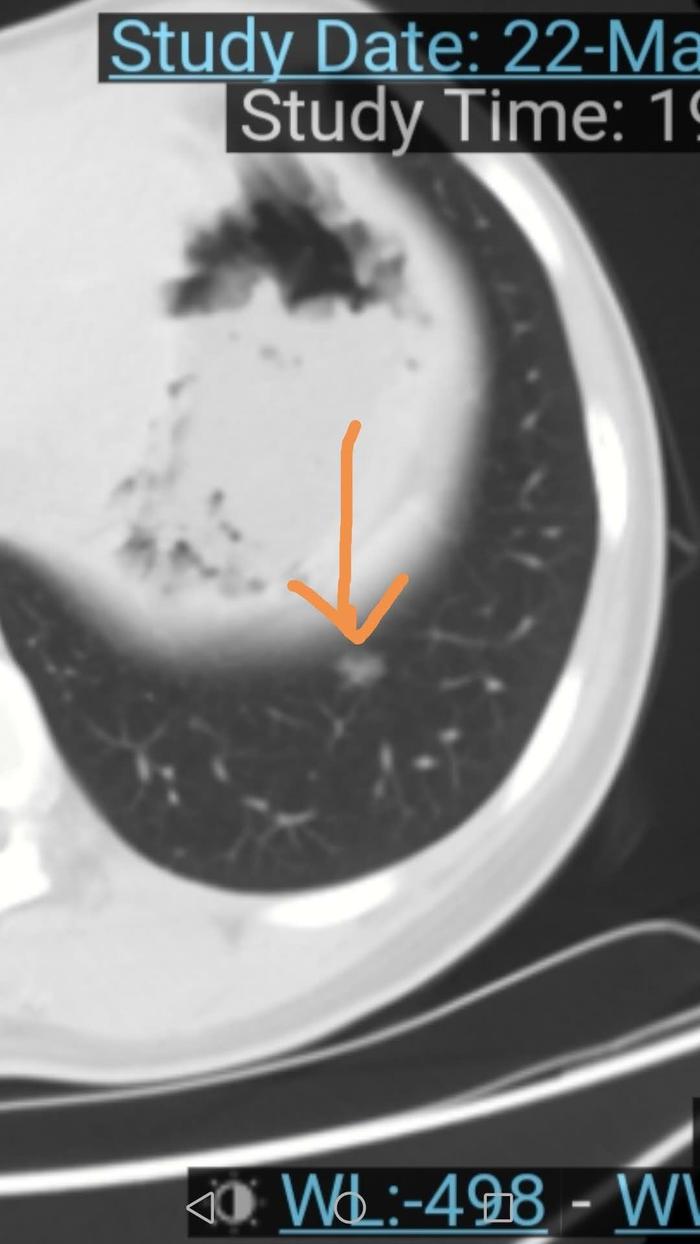

上图红色箭头指的就是左下肺的磨玻璃结节。位于膈肌上方,距离腹腔较近,可以看到排便的胃。注意这个结节密度不均,所以是混合磨玻璃结节;结节内部偏前方有一个小空泡。

上图是放大图,箭头指示的是结节内部偏前方一个圆形低密度区,看起来黑一些,就是一个小空泡。